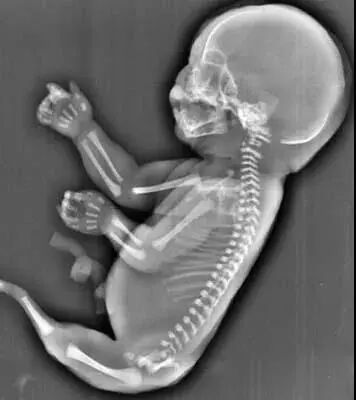

27岁的小美(化名)和相爱多年的男友结婚一年后,一个小生命的悄然到来,给整个大家庭送上了一份惊喜,他们俩感觉太幸福了。然而不幸的事情发生了:小美孕25周超声检查发现胎儿下肢无双腿,双下肢合并外形似鱼尾状,据医生了解,这是一种非常罕见的多发性畸形,双下肢合并外形似鱼尾状,俗称“美人鱼综合症”。

无独有偶,一位40岁的二胎妈妈在一次常规的产检中,发现胎儿下肢是两个大腿骨, 并行排列 ,小腿骨好像有点交叉 。医生介绍正常胎儿的下肢是不停地在妈妈肚子里动的, 呈现一个外八字,像这种情况,医生从医40年也是第一次见,后来,这位宝宝也被确诊为美人鱼综合症。因为多数患病的新生儿出生后,只能存活几个小时,就算活下来,也要接受多次手术治疗。最终,在医院的帮助下,这位二胎妈妈选择了终止妊娠。

由于血液循环系统在子宫中没有正常发育

所以他们的的肾脏和其他器官也难发育完整

生存下来也是堪称奇迹